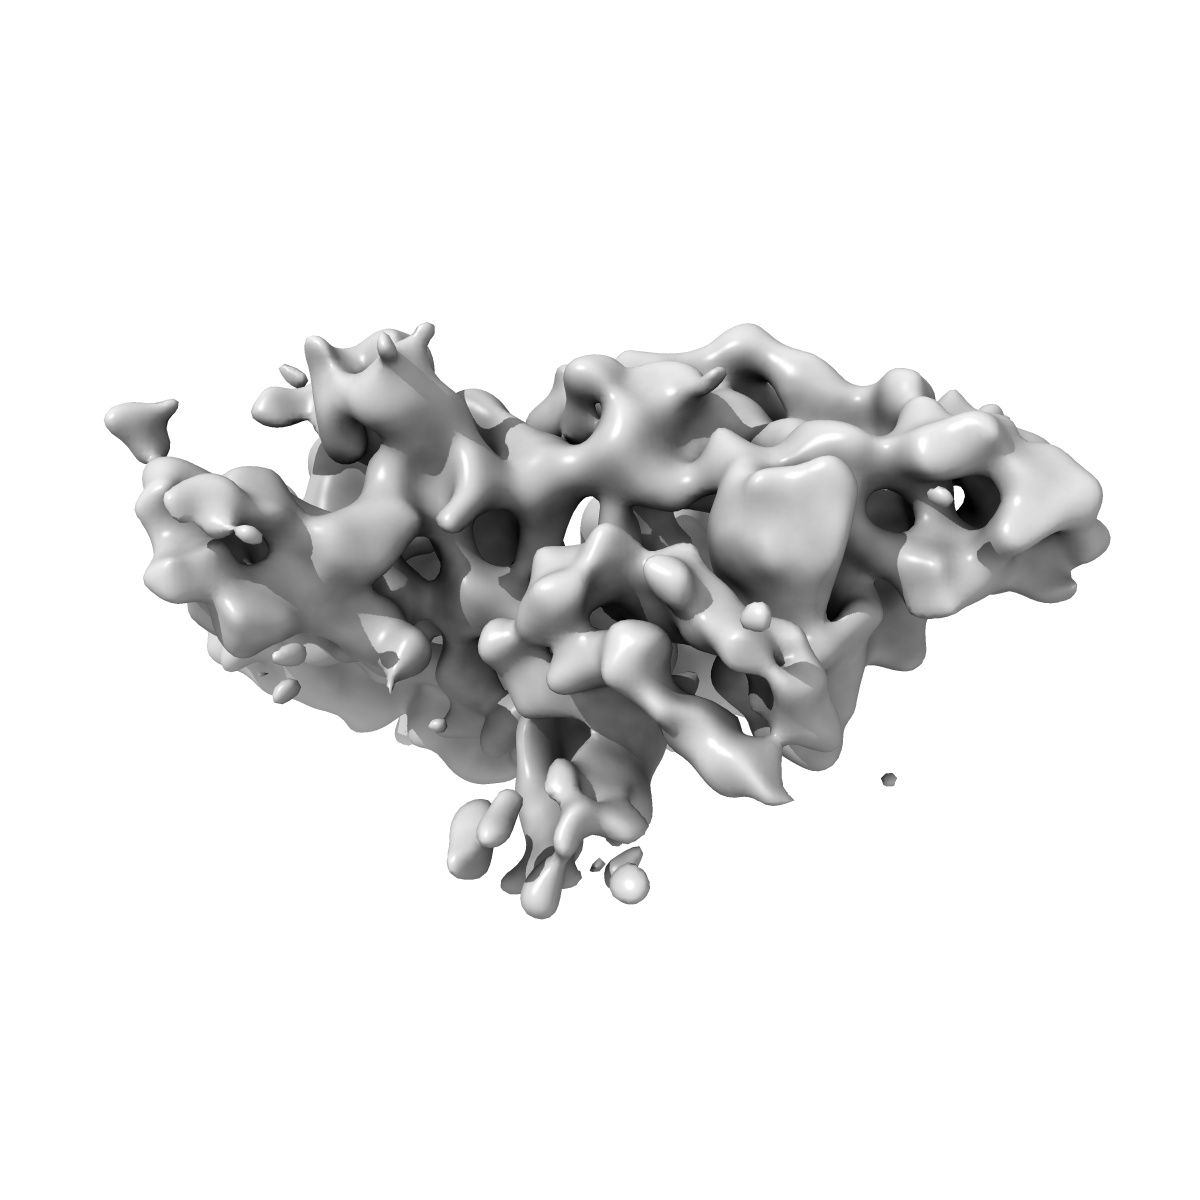

Structure of a partially disrupted IgE high affinity receptor complex bound to an omalizumab variant

Sample: Locked complex of IgE-Fc (G335C) and alpha chain of the high affinity IgE receptor (W156C) bound to clone_7 scFV

Directed evolution of and structural insights into antibody-mediated disruption of a stable receptor-ligand complex.

Pennington LF , Gasser P , Kleinboelting S , Zhang C, Skiniotis G , Eggel A , Jardetzky TS

(2021) Nat Commun , 12 , 7069 - 7069